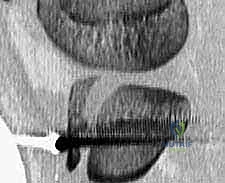

5. التثبيت الداخلي (Internal Fixation)

هنا تبرز مهارة الجراح في اختيار طريقة التثبيت التي لا تضر بصفيحة النمو (إذا كانت لا تزال مفتوحة).

* استخدام البراغي المجوفة (Cannulated Screws): يتم إدخال سلك توجيهي رفيع أولاً، وبعد التأكد من موقعه بالأشعة السينية داخل غرفة العمليات، يتم إدخال برغي أو برغيين من التيتانيوم القوي فوق السلك لتثبيت العظم. يحرص الدكتور هطيف على توجيه البراغي من الأمام إلى الخلف، وفي بعض الأحيان بزاوية مائلة لتجنب اختراق صفيحة النمو قدر الإمكان.